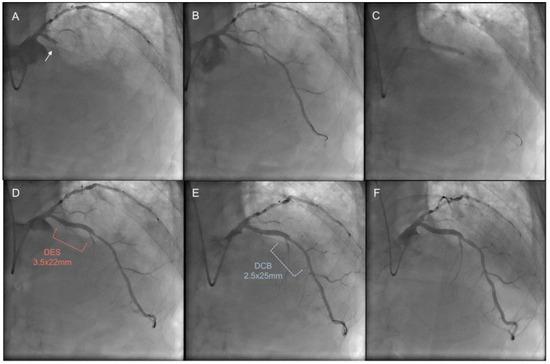

- Jun, E.J.; Shin, E.S.; Teoh, E.V.; Bhak, Y.; Yuan, S.L.; Chu, C.M.; Garg, S.; Liew, H.B. Clinical outcomes of drug-coated balloon treatment after successful revascularization of de novo chronic total occlusions. Front. Cardiovasc. Med. 2022, 9, 821380. [Google Scholar] [CrossRef] [PubMed]

- Köln, P.J.; Scheller, B.; Liew, H.B.; Rissanen, T.T.; Ahmad, W.A.; Weser, R.; Hauschild, T.; Nuruddin, A.A.; Clever, Y.P.; Ho, H.H.; et al. Treatment of chronic total occlusions in native coronary arteries by drug-coated balloons without stenting—A feasibility and safety study. Int. J. Cardiol. 2016, 225, 262–267. [Google Scholar] [CrossRef] [PubMed]